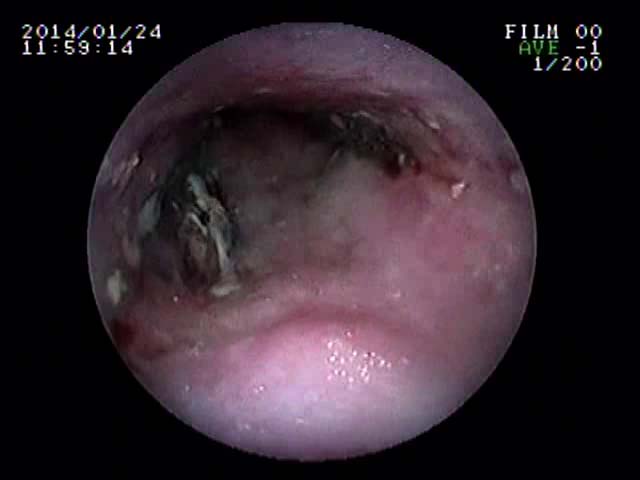

内視鏡のお話(仔牛のあばらぼねガム)

先日、2日前から食欲廃絶のチワワさんが来院しました。そのきっかけが、同居している大型犬のおやつを横取りしたときからとのことでした。話を聞いたら、その後からずっと泡状の液体を吐いているようでした。それは、おそらく唾液をのめなくて突出しているのだと直感しました。

ガムは仔牛のあばら骨ガムだったので、食道停滞を考えました。エックス線を撮影したら、さすがにあばら骨だけあってくっきり咽頭部付近の食道に写っていました。すぐに内視鏡をすすめて処置をはじめたのですが、扁平のガムが食道を拡張させはまり込んで内視鏡鉗子(直径2mm)ではとれませんでした。押して胃内に押し込むことも考えましたがびくともしません。そこで腹腔鏡(硬性鏡)用の鉗子(5mm)を内視鏡と併走させて食道の異物まで到達させ把持することを考え、実施したらなんとかうまくつかめました。場合によっては、開胸手術による食道切開で摘出することも適応になる症例であってもおかしくありませんでした。

これは、今までの経験が生かせた処置ともいえました。麻酔が覚めた本人はケロッとしていて、ごはんを欲しそうな様子でした。この顔をみたとき、ある意味充実感がありました。よかったね、富士ちゃん!

![]() |

食道にはまったガムを腹腔鏡鉗子で取り除いている様子 | 実際とれたあとの食道粘膜の写真(一部炎症とびらんがあります) | 正常の食道粘膜の写真 | 実際とれたあとの写真 (ガムの中にあばら骨があります) |